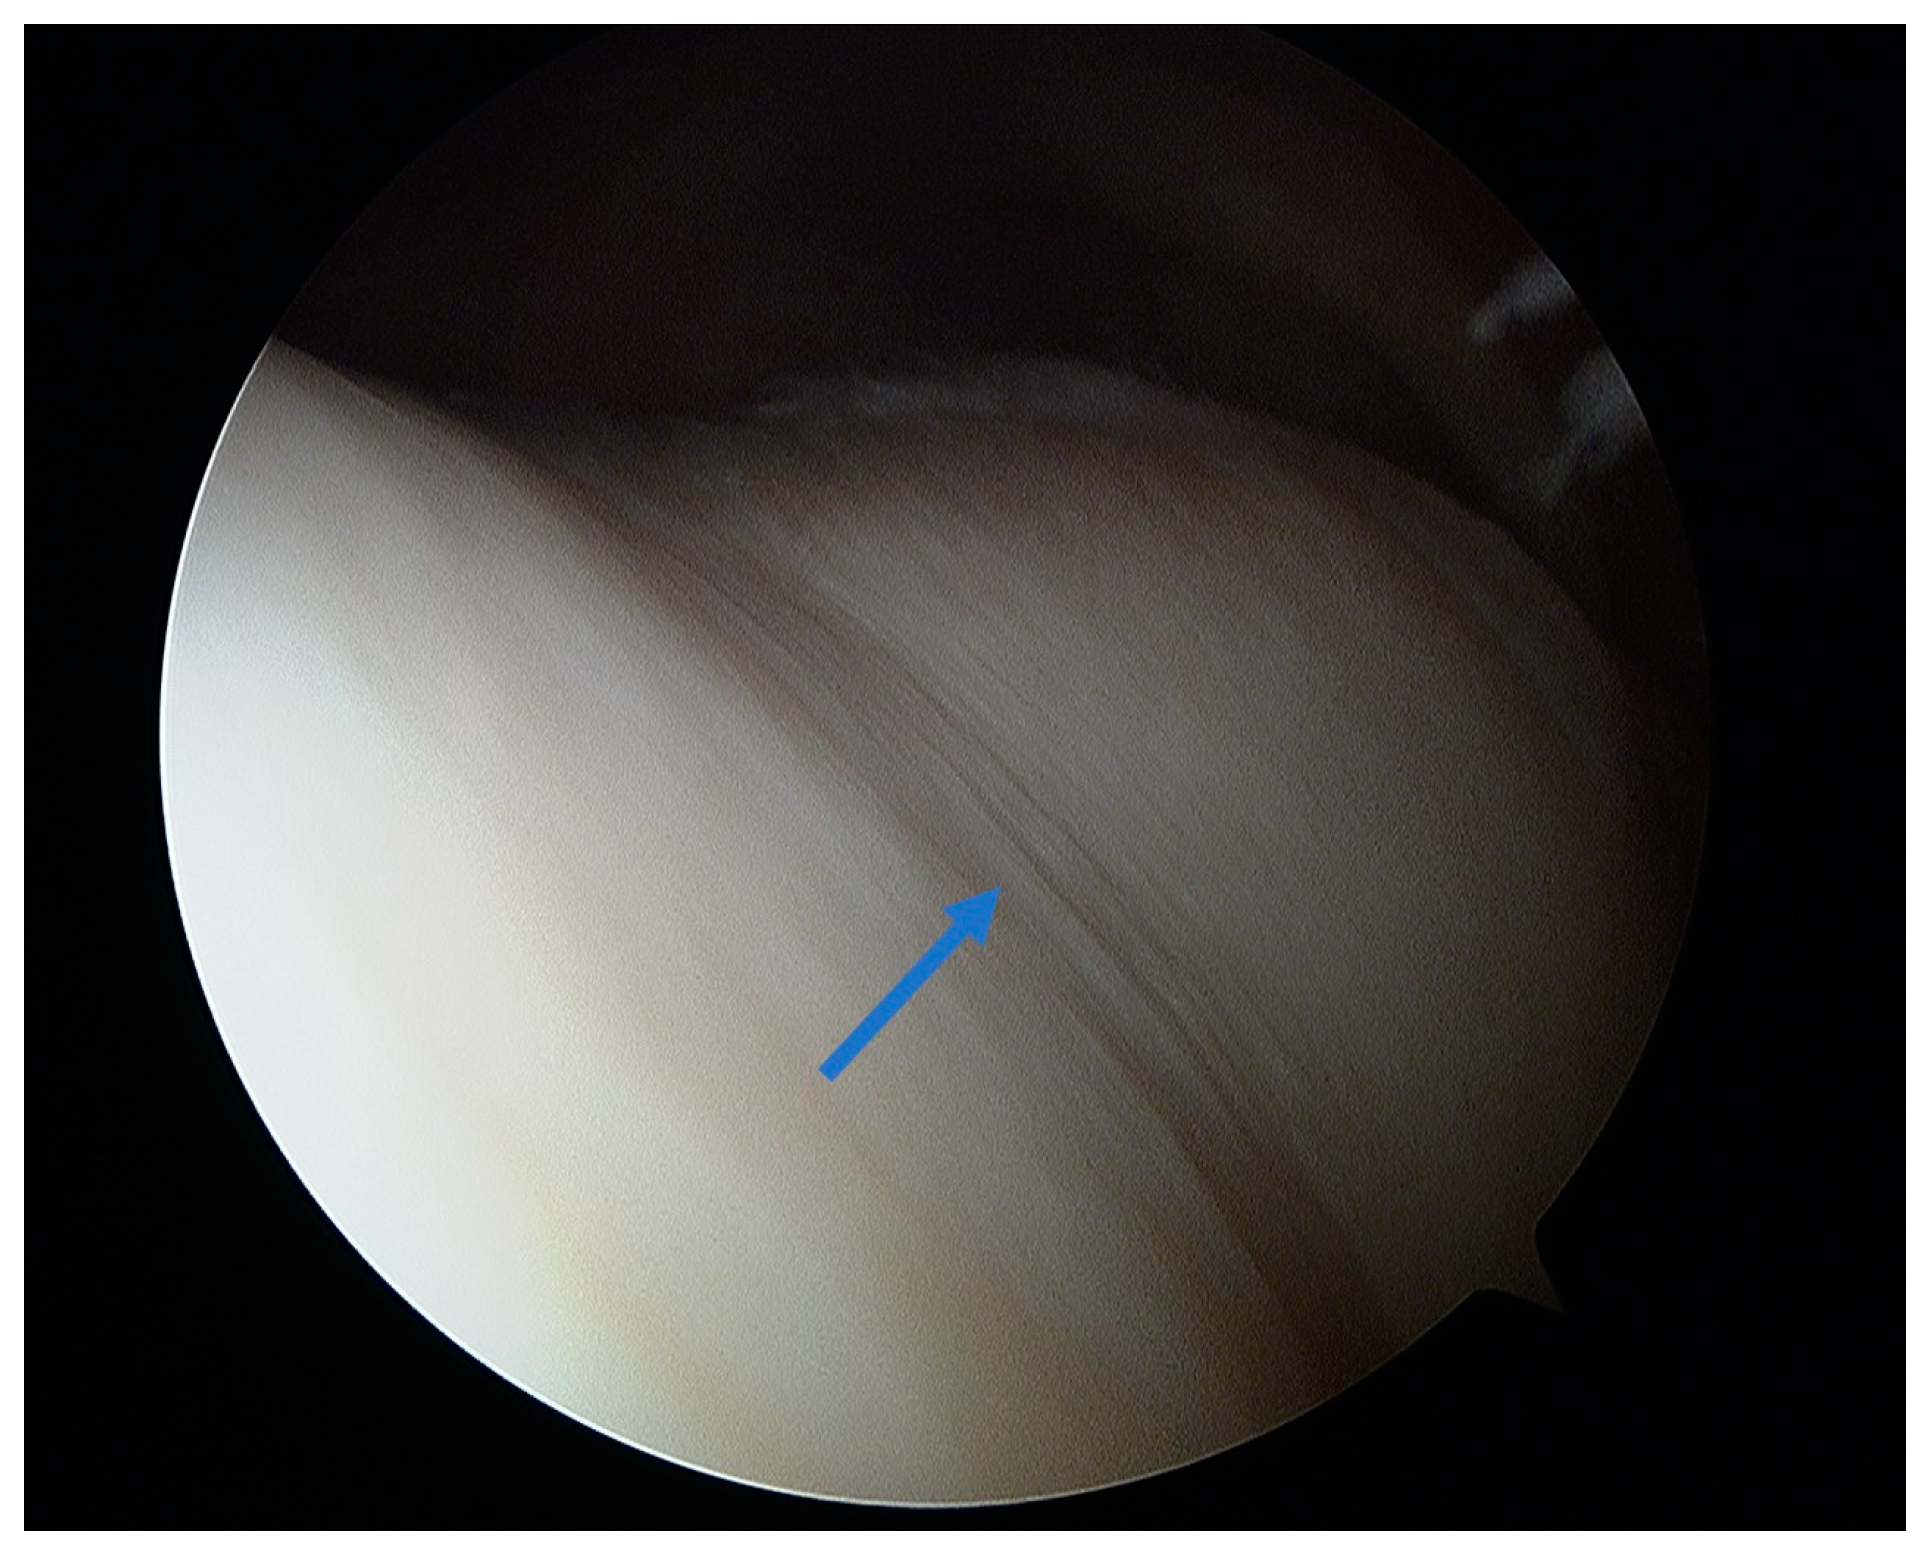

5.1. Microfracture